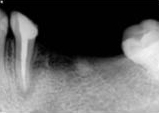

antes depois